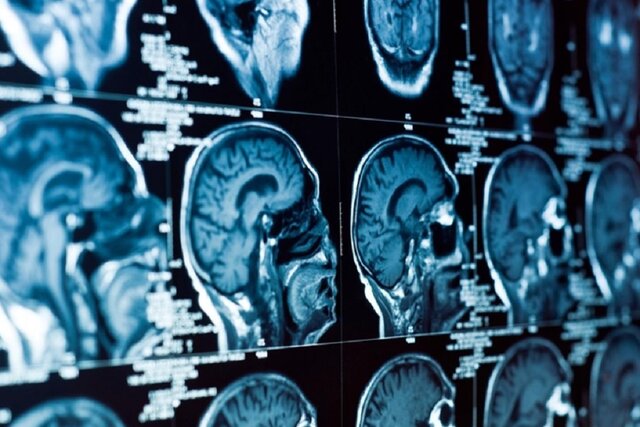

ضعیف شدن واکنش‌پذیری عروق مغزی که ظرفیت انقباض عروق مغزی در واکنش به شرایط فیزیولوژیکی به منظور تنظیم جریان خون است، می‌تواند خطر تخریب عصبی را افزایش دهد. به همین ترتیب، پیامدهای کووید-۱۹ بر عروق مغزی نیز ممکن است بر سلامت مغز تأثیر بگذارند. اگرچه این آسیب حاد با استفاده از تصویربرداری عصبی قابل تشخیص است اما تداوم اثرات بلندمدت آن ناشناخته باقی مانده‌ است.

پژوهشگران مشاهده کردند که ناهنجاری عروق مغزی، ماهها پس از بستری شدن در بیمارستان به دلیل کووید-۱۹ حاد ادامه داشته است. محل وقوع این ناهنجاری‌ها در نواحی جانبی، پیشانی و گیجگاهی مغز بود که تا حدی با اختلال عملکرد عروق مغزی مرتبط با افزایش سن و بیماری آلزایمر مطابقت دارد.